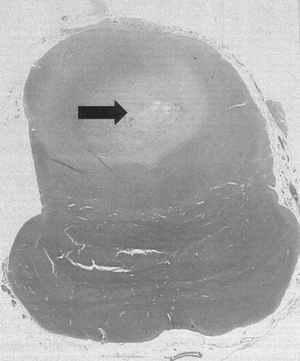

The "Sudden, Unexpected Death Related to Viral Myocarditis" discusses this very often difficult to diagnose condition. There are seventy-four references the most recent 2003.

The last chapter discusses "Subendocardial Hemorrhages" Again this is an arcane issue which is rarely discussed but is encountered from time to time in forensic cases. There are sixty-seven references the most recent is 2002.